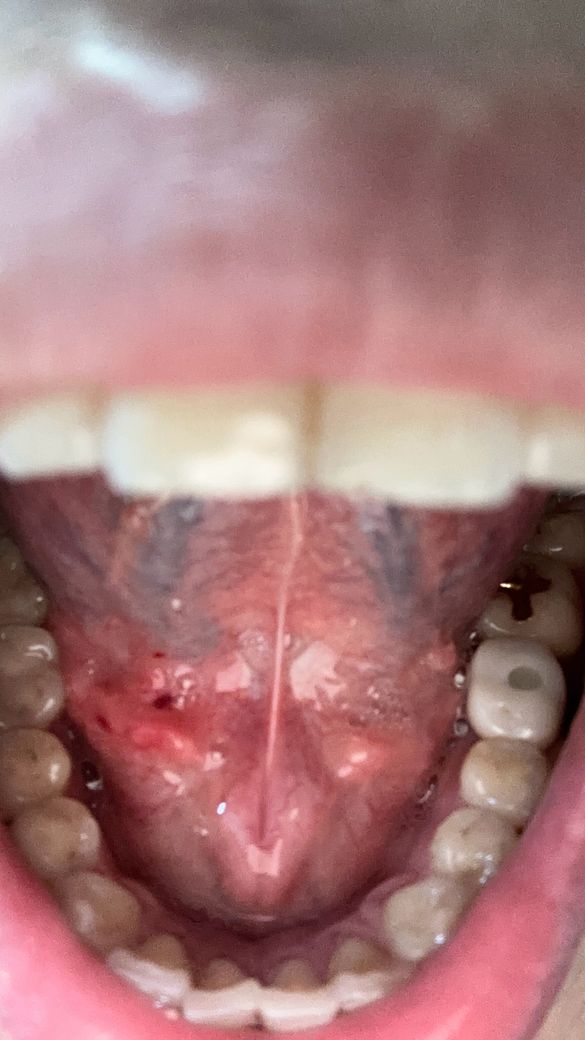

양치하다가 칫솔로 눌렀는데 피나는거처럼 됬어요

빨갛게 된부분이 있는것같고 그래서 이거 병원가봐야되는지 그냥 냅둬도 괜찮음지 궁금해요 어떻게하는게 좋을까요?? 병원은 무슨과인가요?

• 3번 째 사진

양치 중 칫솔로 인해 잇몸이 붉어지고 피가 나는 것은 잇몸 염증의 초기 증상일 수 있습니다. 칫솔질 시 잇몸에 과도한 힘이 가해지거나, 치석이나 치태가 쌓여 잇몸이 자극받았을 가능성이 있습니다. 우선 2~3일 정도는 부드러운 칫솔모를 사용하여 잇몸에 자극을 최소화하고, 치실이나 치간칫솔을 사용하여 꼼꼼하게 치아 사이를 청결하게 관리해주세요.

만약 며칠 후에도 증상이 호전되지 않거나, 붓기나 통증이 심해진다면 치과에 방문하여 정확한 진단을 받아보는 것이 좋습니다. 치과에서는 잇몸 상태를 확인하고 필요한 경우 스케일링이나 다른 치료를 통해 잇몸 건강을 회복할 수 있습니다.